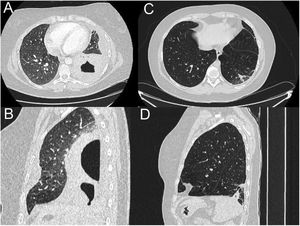

Since blood tests and X-rays were altered, a computed tomography (CT) pulmonary angiogram was performed (Fig. 1) to rule out pulmonary thromboembolism. Instead, an extensive consolidation that occupies the entire left lower lobe with two cavitations inside with air-fluid level was found, the largest one of 7cm. These findings suggested necrotizing pneumonia with lung abscesses (A and B).

CT pulmonary angiogram. Extensive consolidation that occupies the entire left lower lobe with two cavitations inside with air-fluid level, the largest of 7cm, suggesting necrotizing pneumonia with lung abscesses (A and B). Complete resolution of the pneumonic process visualizing in its place an area with fibro-atelectatic changes as a residual finding (C and D).

New thoracic computed tomography scan was done 4 months later, which showed consolidation and cavities resolution and residual fibrosis-atelectasis. Lung function tests were normal.